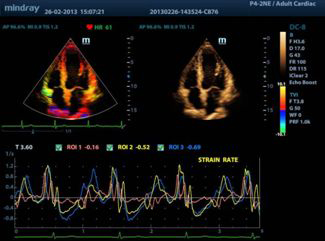

Режим деформации / скорости деформации

Позволяет получить полную оценку ишемической болезни сердца посредством визуализации показателей деформации / скорости деформации, обеспечивая детальное сопоставление различных участков миокарда.